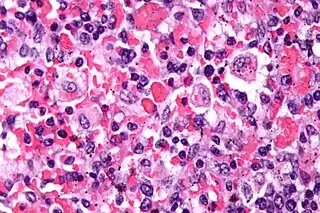

![]() Microfotografia de la muestra de tejido de un paciente afectado por linfohistiocitosis hemofagocítica. | ||

Se caracteriza por proliferación incontrolada de linfocitos T activados y macrófagos que segregan gran cantidad de linfoquinas, produciéndose el fenómeno de hemofagocitosis,[Nota 1] las células que proliferan no son malignas, es decir la enfermedad no tiene relación alguna con el cáncer. Los órganos afectados son principalmente la médula ósea, hígado bazo y sistema nervioso central.